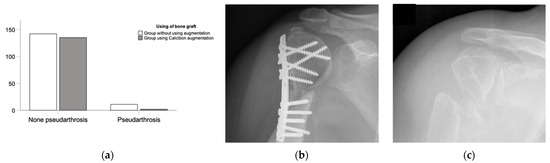

Figure 4.

Overview of pseudarthrosis post-surgery. (a) Rate of pseudarthrosis in the ED group compared with the rate of pseudarthrosis in the NHA group with significant differences. (b) An example of the clinical examination of a recent fracture treatment. (c) Conventional radiograph of a pseudarthrosis 18 years post-trauma by X-ray.

Figure 5.

Summary of selected complications demonstrating the differences between the empty defect (ED) treatment (light grey) and the calcium phosphate augmentation (CP) group (dark grey). (a) Number of all complications in the ED and the CP cohort with significant differences (p = 0.001). (b) Comparing pseudarthrosis and other complications in ED and the CP cohort demonstrated less pseudarthrosis and fewer other complications in the CP treatment cohort (p < 0.001). (c) Infection and necrosis demonstrated insignificantly fewer infections in the ED group compared to the CP treatment group.